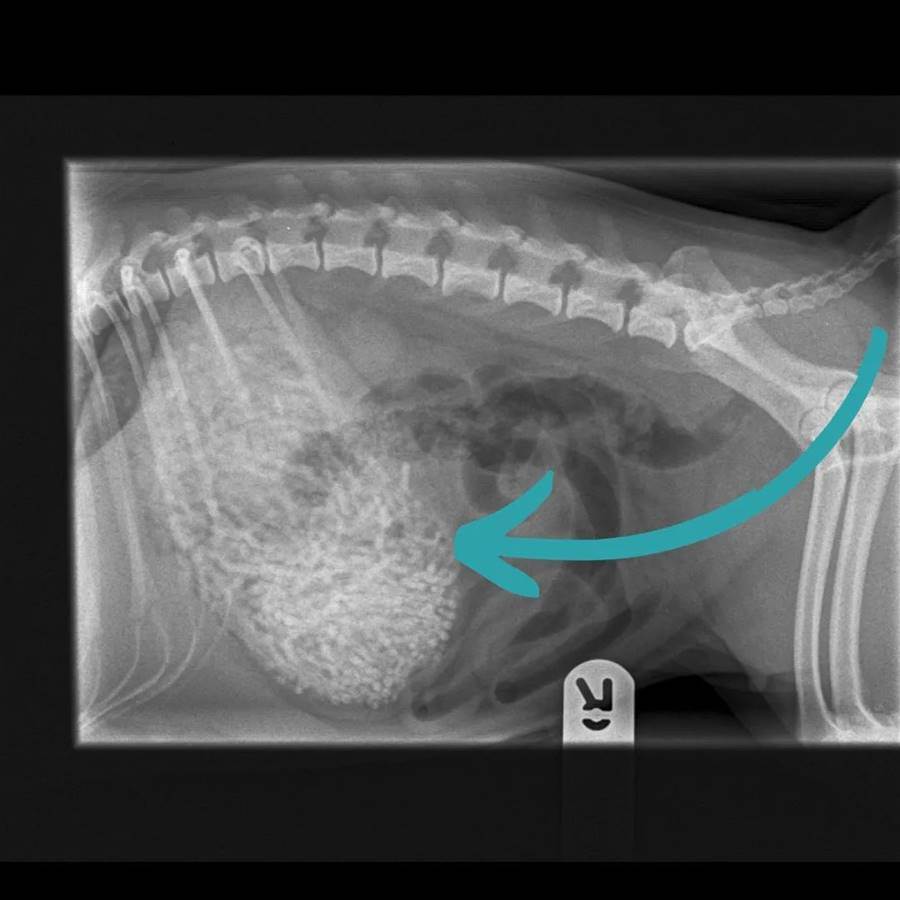

撿屎官擔心它出什麼問題,便帶去寵物醫院檢查,結果一看嚇一大跳,拍片子發現它腹部有很多奇怪的東西!

醫生緊急手術,進一步的檢查,最后竟取出50多條發帶皮筋,至少有200g,驚呆眾人。